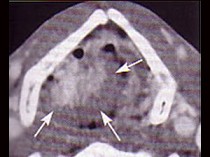

4.下面是一頸部CT圖,其中結構標志不正確的是  (    )

正確答案:D

6.CT檢查見下圖,進一步的檢查是  (    )